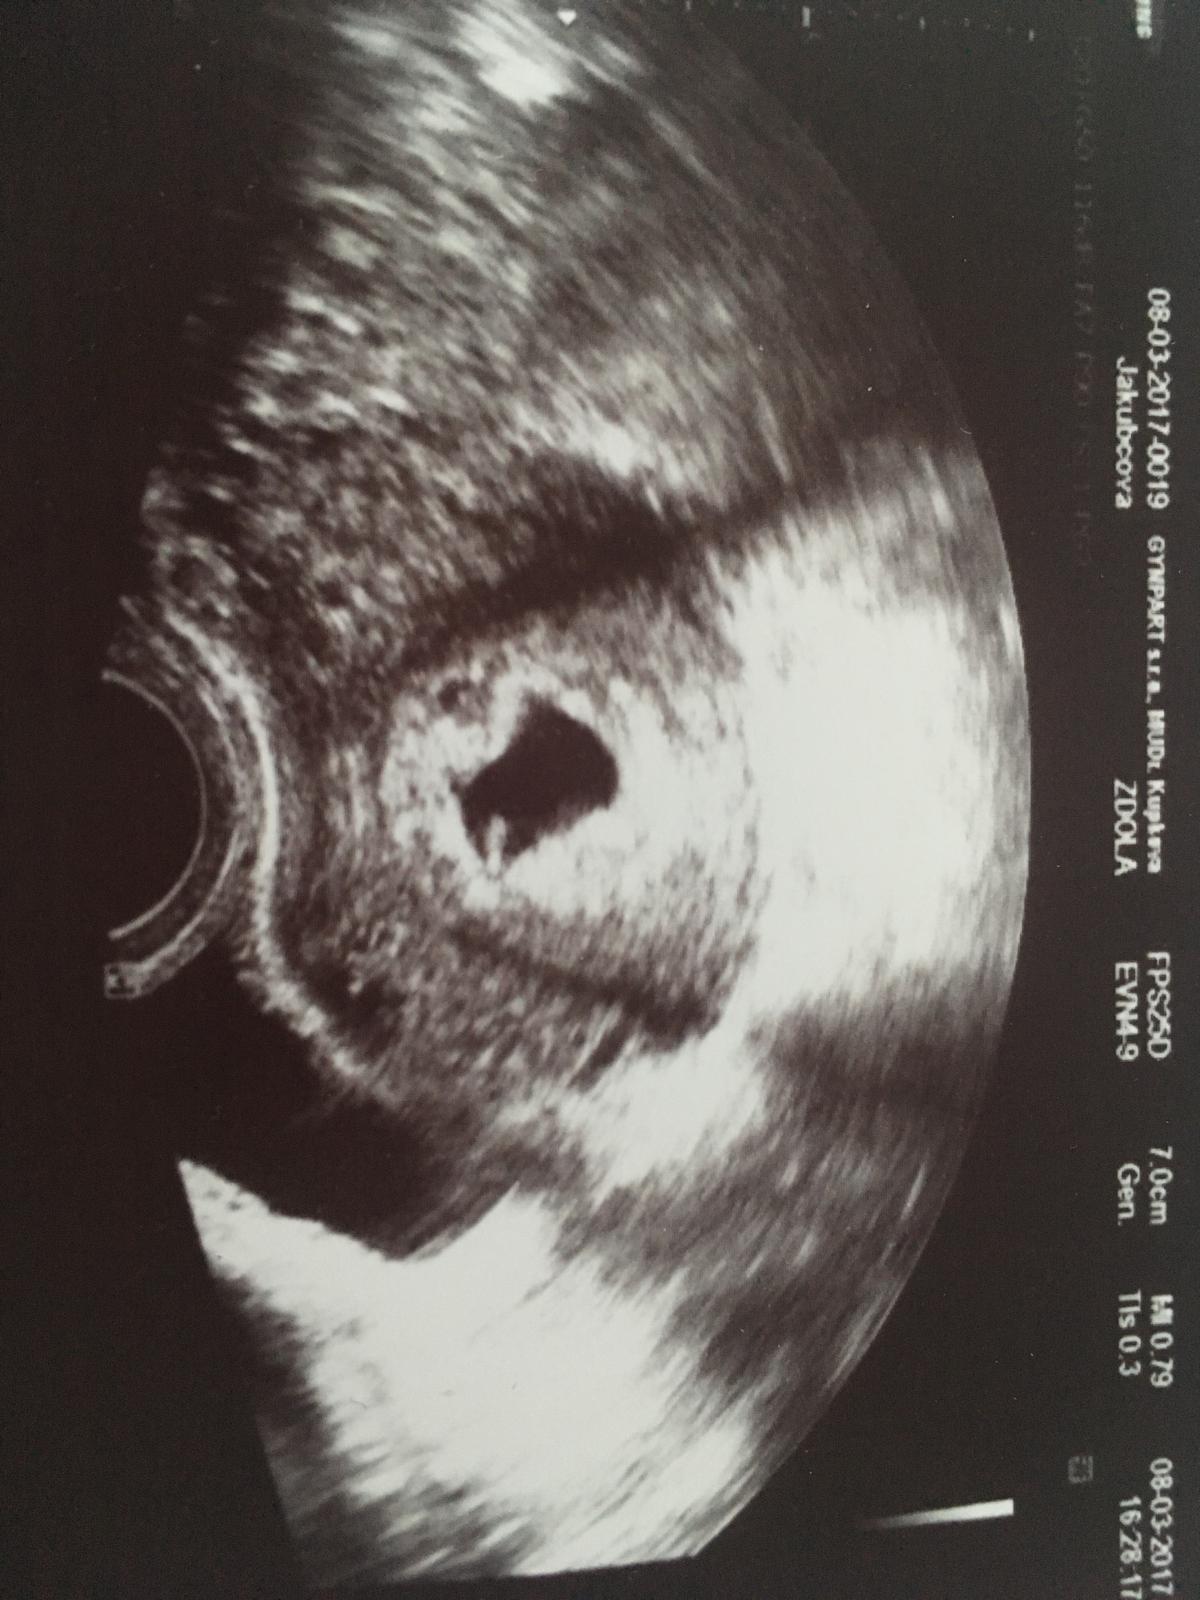

Jinak jsem holky dnes po kontrole a vše v pořádku 🙂 Ukázala mi žloutkový vacek i plod a jak říkala ,, ševelí '' se to tam 😂

Tak snad bude vse OK 🙂